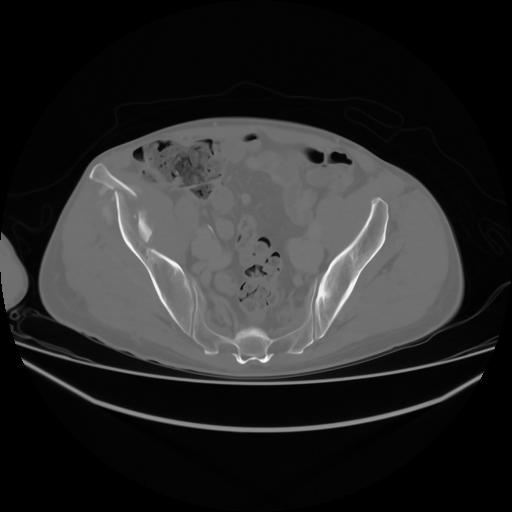

4 CUERPO,CE,Axial,3.0,CUERPO,,